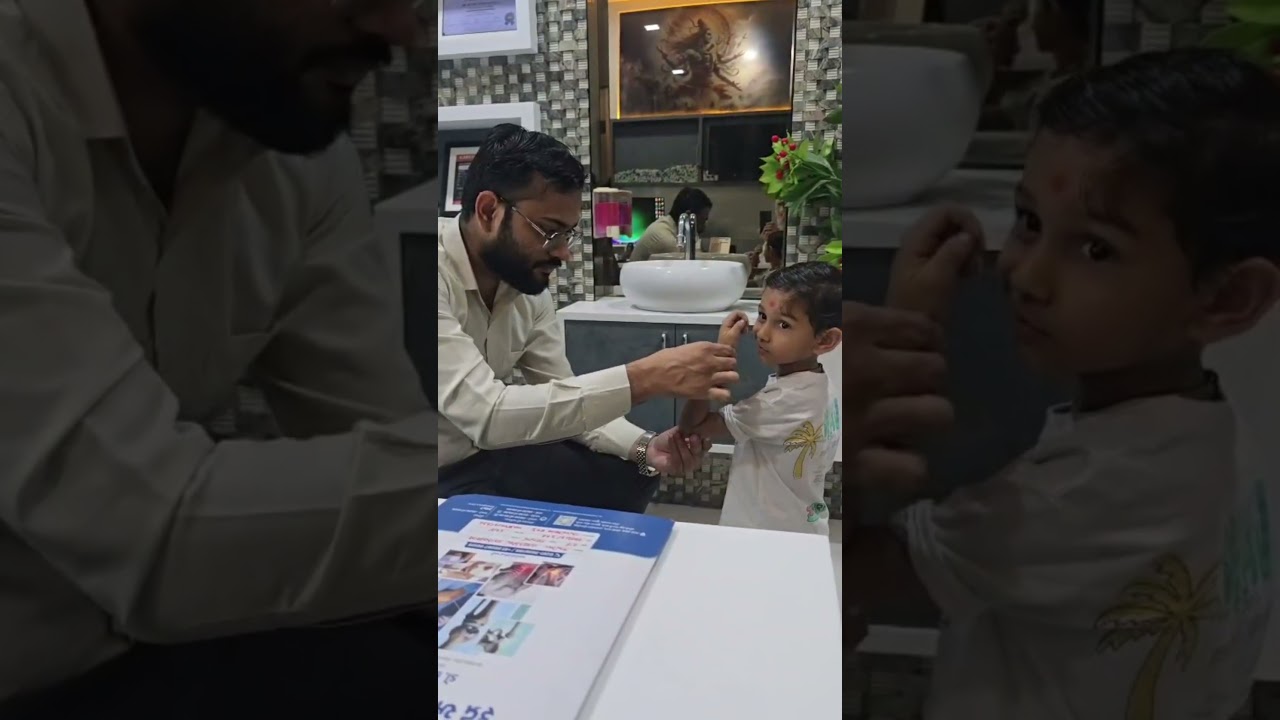

Rudra Orthopedic Hospital is one of the leading Orthopaedic Hospitals in Surat, providing advanced bone, joint, spine, and trauma care under the expert guidance of Dr. Keval S. Italiya, Consultant Orthopaedic Surgeon.

Dr. Keval S. Italiya is a highly skilled and dedicated Orthopaedic Surgeon in Surat known for accurate diagnosis, advanced surgical expertise, and patient-centered treatment approach

Dr. Keval S. Italiya is a highly skilled and dedicated Consultant Orthopedic Surgeon known for his precise diagnosis, ethical medical practice, and patient-centered approach.

Dr. Italiya has extensive expertise in trauma care, joint replacement surgeries (knee & hip), fracture management, arthritis treatment, and spine-related conditions. His approach focuses on long-term recovery and functional restoration rather than temporary pain relief.